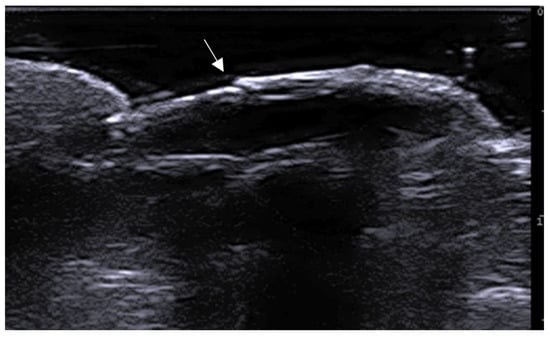

- Ogueta, I.; Navajas-Galimany, L.; Concha-Rogazy, M.; Álvarez-Véliz, S.; Vera-Kellet, C.; Gonzalez-Bombardiere, S.; Wortsman, X. Very High- and High-Frequency Ultrasound Features of Cutaneous Larva Migrans. J. Ultrasound Med. 2019, 38, 3349–3358. [Google Scholar] [CrossRef] [PubMed]